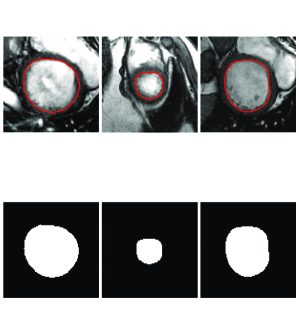

where is the labeled data corresponding to the th image. The labeled data are binary masks created from manual segmentations drawn by experts. Fig. 5 depicts three examples of input images and corresponding labels used for training of the stacked-AE. Note that the binary mask is unrolled as vector to be used during optimization.

We utilize and train a stacked-AE, depicted in Fig. 6, to infer the shape of the LV. The stacked-AE has one input layer, two hidden layers, and one output layer. The sub-image obtained from the previous block is sub-sampled and unrolled as vector and fed to the input layer. The hidden layers build the abstract representations by computing and . The output layer computes to produce a binary mask. The binary mask is black (zero) everywhere except at the borders of the LV. Here, , and are trainable matrices and vectors that are obtained during the training process, as detailed in the next section.